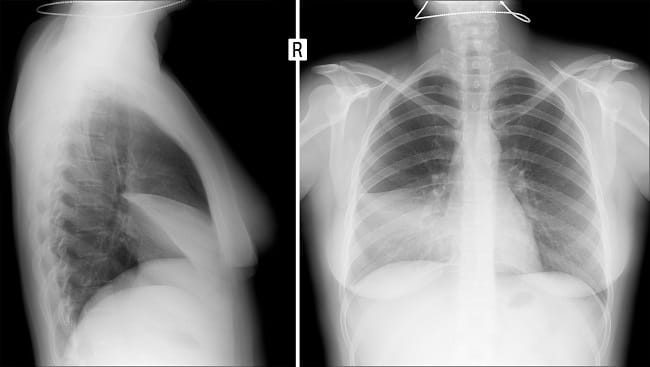

Untuk melihat adanya peradangan pada pleura atau paru-paru, dokter akan melakukan pemindaian pada paru-paru dengan foto Rontgen dada, CT scan dada, atau USG dada. Pemeriksaan tersebut juga bisa mendeteksi penumpukan cairan di ruang antar pleura.